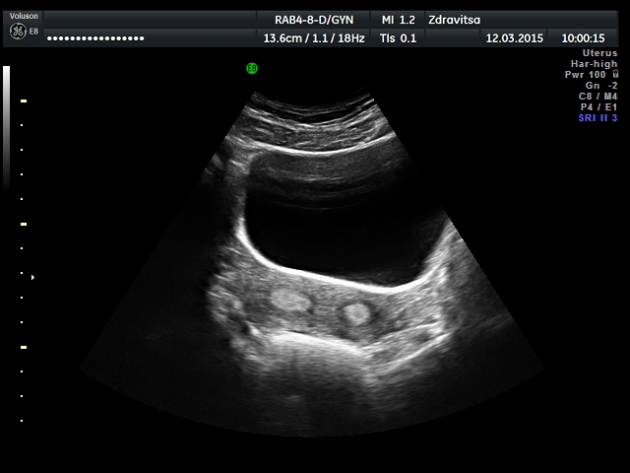

Случай №2. Девушка 22 лет, жалобы на НОМЦ по типу альгоменореи в течении последних трех месяцев.1-я фаза цикла.